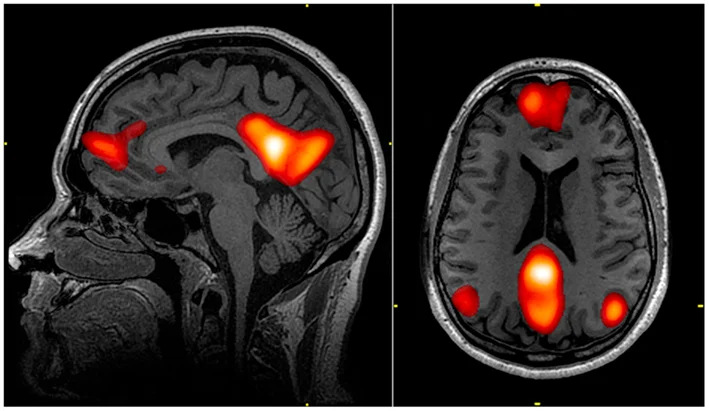

First, the researchers administered a series of cognitive tests, like the California Verbal Learning Test (CVLT) and the Trail Making Test (TMT). Seventeen members of the older group scored at or above the mean scores of the younger group. That is, these 17 could be considered super-agers, performing at the same level as the younger study participants. Aside from these individuals, members of the older group tended to perform less well on the cognitive tests. Then, the researchers scanned all participants' brains in an fMRI, paying special attention to two portions of the brain: the default mode network and the salience network.

The default mode network is, as its name might suggest, a series of brain regions that are active by default — when we're not engaged in a task, they tend to show higher levels of activity. It also appears to be very related to thinking about one's self, thinking about others, as well as aspects of memory and thinking about the future.

The salience network is another network of brain regions, so named because it appears deeply linked to detecting and integrating salient emotional and sensory stimuli. (In neuroscience, saliency refers to how much an item "sticks out"). Both of these networks are also extremely important to overall cognitive function, and in super-agers, the activity in these networks was more coordinated than in their peers.

An image of the brain highlighting the regions associated with the default mode network.